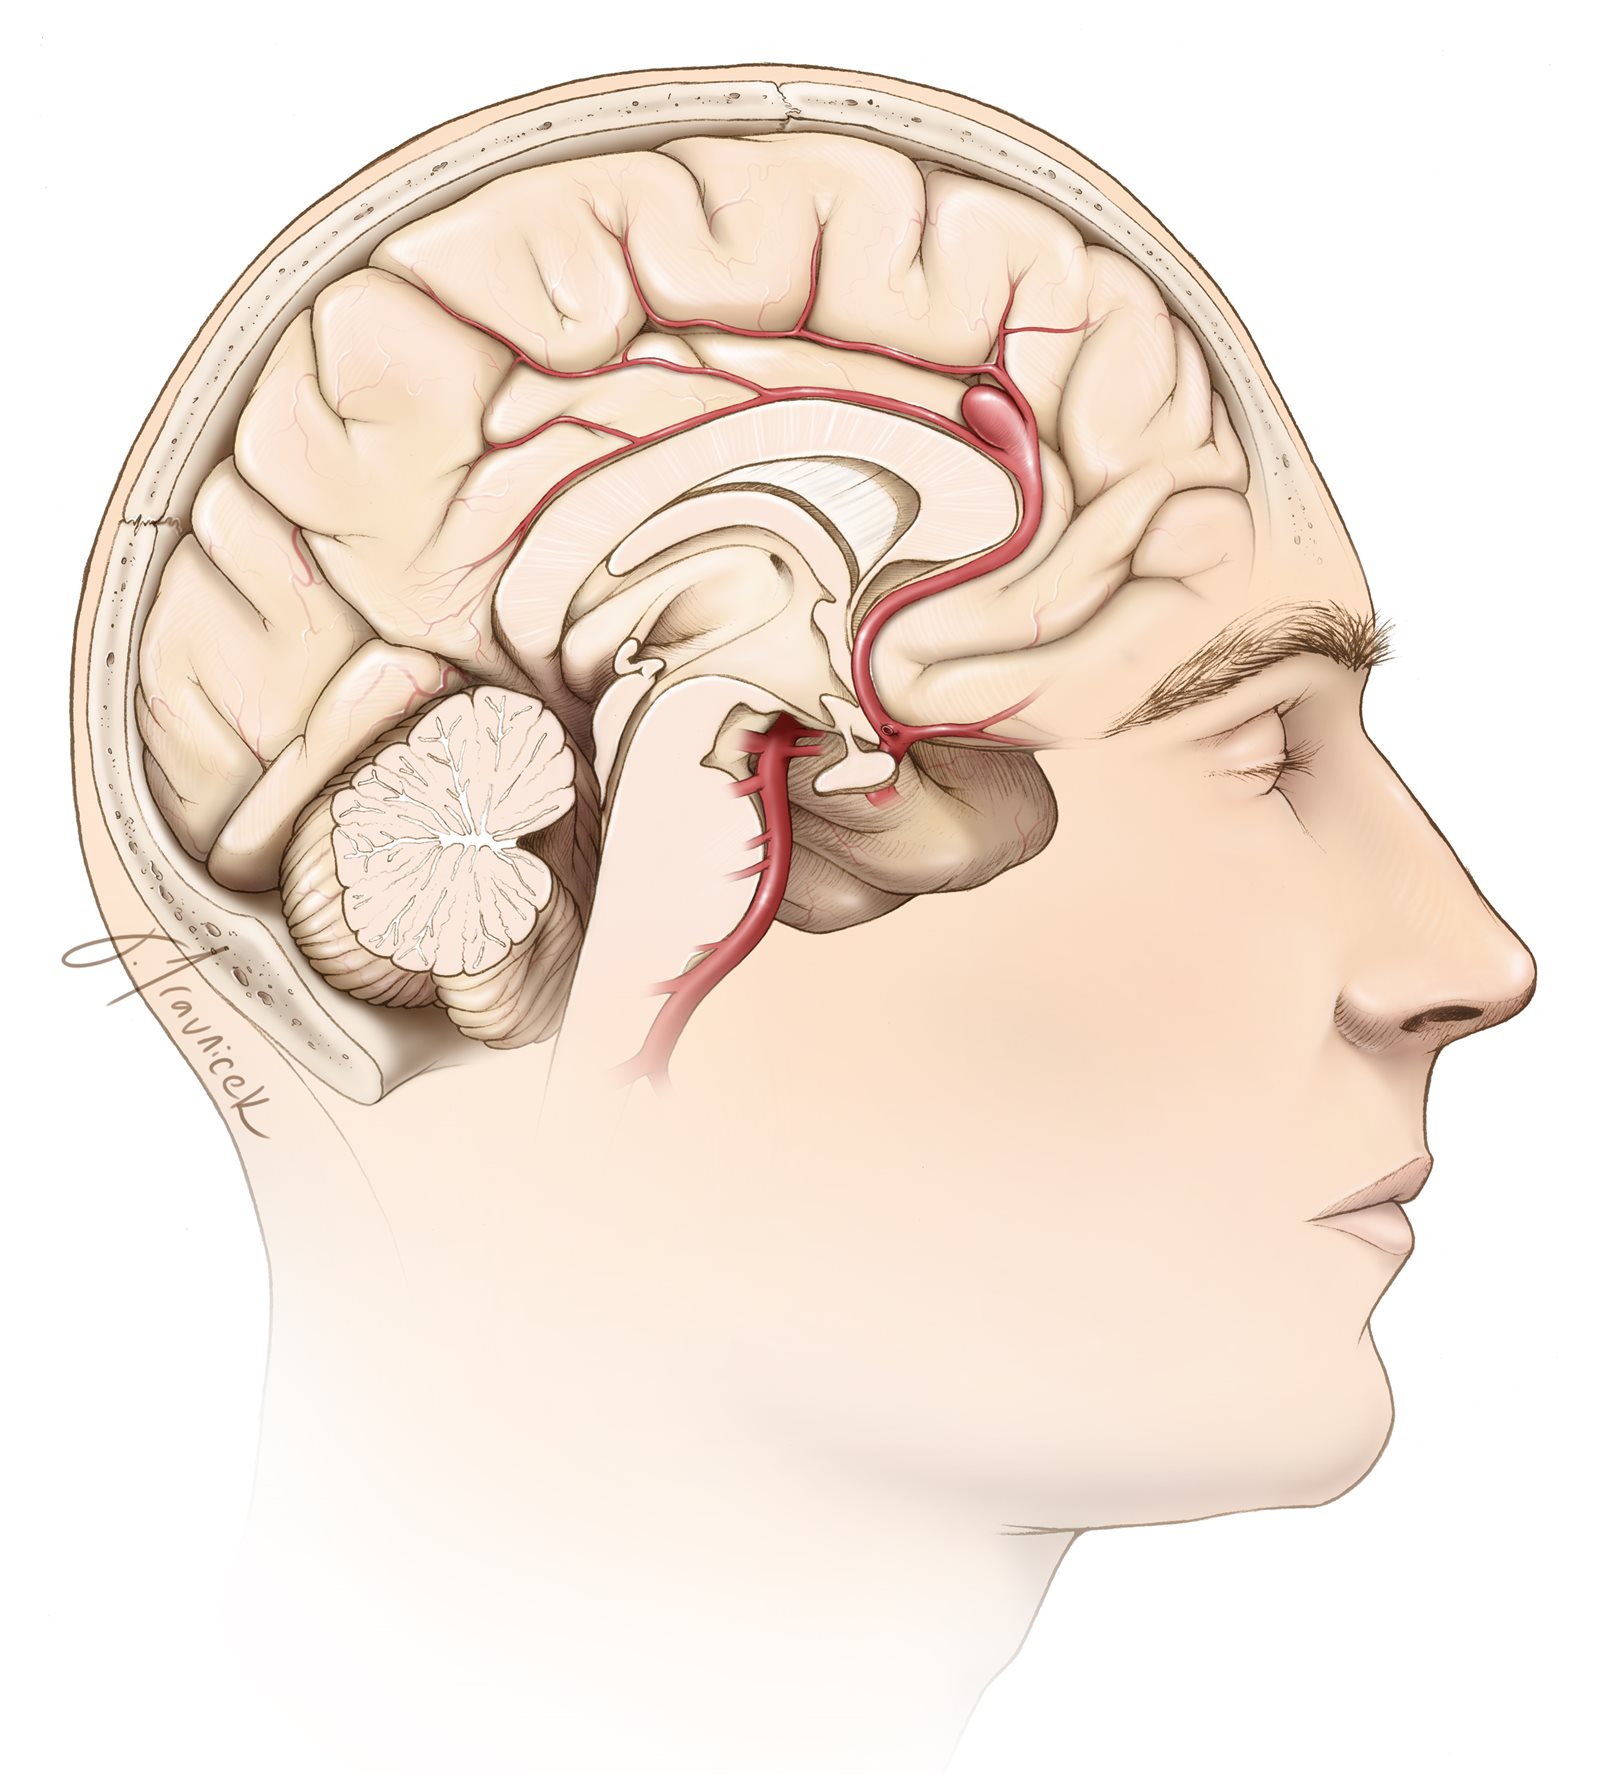

تمدد الأوعية الدموية في الدماغ

تمدد الأوعية الدموية في الدماغ هو ضعف موضعي يشبه البالون في الأوعية الدموية التي يمكن أن تتمزق وتكون قاتلة.

إن PEDV عبارة عن «دعامة لتحويل التدفق» تتوافق مع شكل الشريان الذي يغطي مدخل تمدد الأوعية الدموية لمنع دخول الدم.

الجهاز عبارة عن هيكل أنبوبي معدني يتم إدخاله في الشرايين باستخدام أنابيب بلاستيكية صغيرة (القسطرة) يتم تمريرها بجوار تمدد الأوعية الدموية في الدماغ تحت توجيه الصورة.